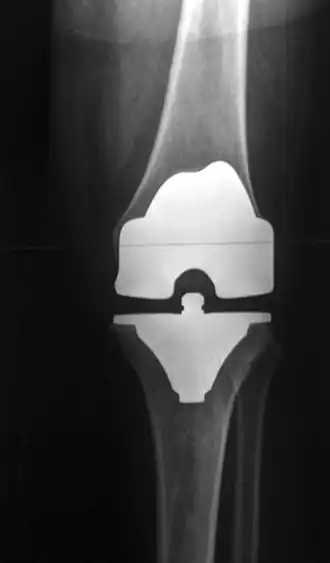

Een kunstgewricht is een kunstmatig gewricht dat dient ter vervanging van natuurlijke gewrichten, die door slijtage of ziekte niet meer functioneren.

Kunstgewrichten worden toegepast voor heupen, knieën, schouders,ellebogen enkels en polsen.

Kunstheupen zijn zeer succesvol, gevolgd door knieën, maar ook vervangende kunstschouders, -enkels en -polsen winnen terrein. In de rug worden ook versleten of beschadigde (tussen)wervelschijven meer en meer vervangen, maar door de vele zenuwbanen en dergelijke is dat niet zonder risico.